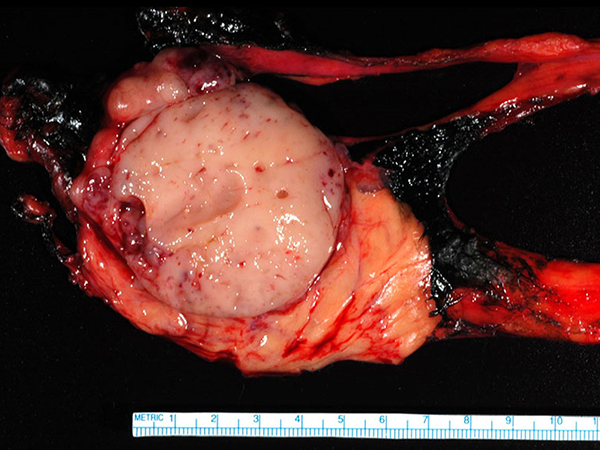

Thymoma, WHO typeB1, forming a 6.5 X 6.4 X 4.9 cm mass.

In the current case, gross evaluation (Figure 2) reveals a fleshy, lobulated, tan-pink solid and focally cystic mass with adjacent thymus tissue. Low power microscopic evaluation (Figure 8) shows a dense lymphoid infiltrate with a fibrous capsule and hypocellular fibrous septa. Also in figure 8, an area of paler tissue (arrow), a so-called “medullary island”, is identified along with Hassall corpuscles (Figure 9 arrow). Figure 10 shows scattered epithelioid cells (arrows). These morphologic features are consistent with a WHO type B1 thymoma.